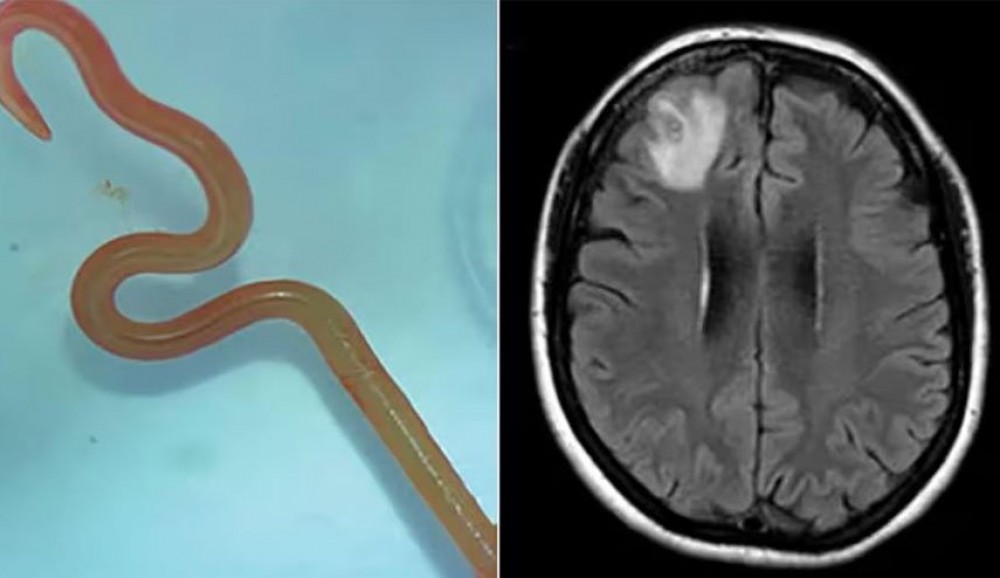

العثور على دودة حية داخل دماغ امرأة!

عثر الأطباء على دودة حية داخل دماغ امرأة في حالة نادرة وتعتبر الأولى من نوعها في العالم.

وقام الأطباء بسحب دودة حية طولها 8 سم توجد عادة في الثعابين من دماغ امرأة تبلغ من العمر 64 عامًا من جنوب شرق نيو ساوث ويلز باستراليا.

وبحلول عام 2022، شملت أعراضها أيضًا النسيان والاكتئاب، مما دفعها إلى إحالتها إلى مستشفى كانبيرا حيث كشف فحص التصوير بالرنين المغناطيسي لدماغها عن وجود تشوهات تتطلب عملية جراحية.